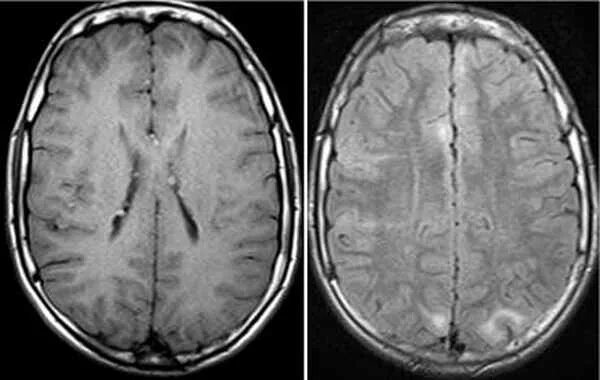

Туберкулезный склероз